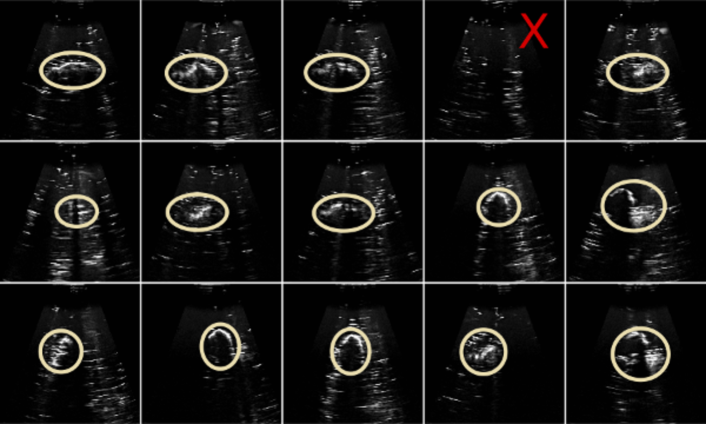

Figure 1 shows predicted reward sequences for sample expert demonstration traces held out from model training. It is clear that the ranking reward model captures the general improvements in image quality that occur as the demonstrator searches for a good scanning view, and that some searching is required before a good viewpoint is found. Importantly, the slack in the pairwise ranking model, combined with the model assumption that similar images result in similar rewards, allows for these peaks and dips in reward to be modelled, as probabilistic temporal ranking does not assume monotonically increasing rewards.

We qualitatively assessed the image regions and features identified using the reward model using saliency maps (Figure 1d), which indicated that the proposed approach has learned to associate the target object with reward.

Trials were repeated 15 times for each approach, alternating between each, and ultrasound gel was replaced after 10 trials. Each trial ran for approximately 5 minutes, and was stopped when the robot pose had converged to a stable point, or after 350 frames had been observed. A high quality ultrasound scan is one in which the contours of the target object stand out as high intensity, where the object is centrally located in a scan, and imaged clearly enough to give some idea of the target object size (see Figure 2).

As shown in Figure 11, the probabilistic temporal ranking model consistently finds the target object in the phantom, and also finds better rated images. Mean and standard deviations in image ratings were obtained using the rating model (see above) trained for reward evaluation using human image preference comparisons. The maximum entropy approach fails more frequently than the ranking approach, and when detection is successful, tends to find off-centre viewpoints, and only images small portions of the target object.